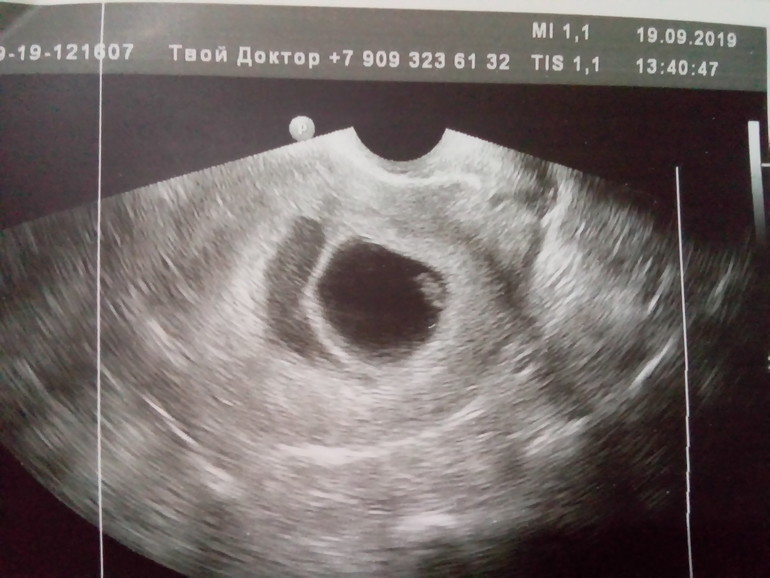

Почистили в срочном порядке, так как по УЗИ эмбрион замер 1,5 недели назад, ждать больше нельзя было.

Мы ждали с мужем на УЗИ хороших новостей, хотели видео снять движения плода, а тут узистка молчит и молчит, тяжело ей было во 2й уже раз сообщать о замирании плода. Муж расстроился так, что уже не хочет больше детей, я думаю мужчины тяжелее переносят потери, так как они всё держат в себе, мы то можем поплакать.